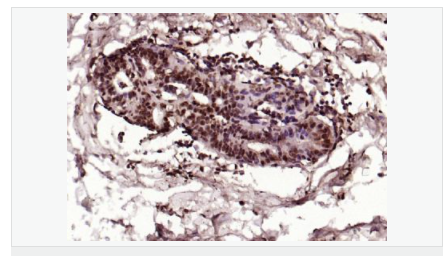

交叉反應:Human,Mouse,Rat(predicted:Dog,Pig,Rabbit,GuineaPig) 推薦應用:IHC-P,IHC-F,ICC,IF,Flow-Cyt,ELISA

| 產(chǎn)品應用 | ELISA=1:5000-10000 IHC-P=1:100-500 IHC-F=1:100-500 Flow-Cyt=1μg/Test ICC=1:100 IF=1:100-500 (石蠟切片需做抗原修復) not yet tested in other applications. optimal dilutions/concentrations should be determined by the end user. |